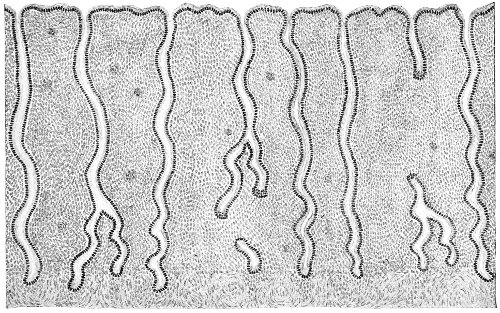

Several varieties of acute vaginitis may be recognized—the simple, the granular, the senile, and the emphysematous. It is unusual to find the entire surface of the vagina involved. The disease is confined to areas or patches separated by healthy tissue.

In simple vaginitis the inflamed membrane remains smooth.

In granular vaginitis, which is the variety usually seen, the papillæ are infiltrated with small cells, and are much enlarged, so that the inflamed surface has a granular appearance.

Acute vaginitis is accompanied by dull pain and a sense of fulness in the pelvis. The discomfort is increased by standing, walking, defecation, and urination. There is a free discharge of serum or pus, which may be tinged with blood. The character of the discharge depends upon the variety and the period of the disease. Inspection, which can best be made through the Sims speculum, with the woman in the Sims or knee-chest position, shows the characteristic lesions of inflammation of the mucous membrane.